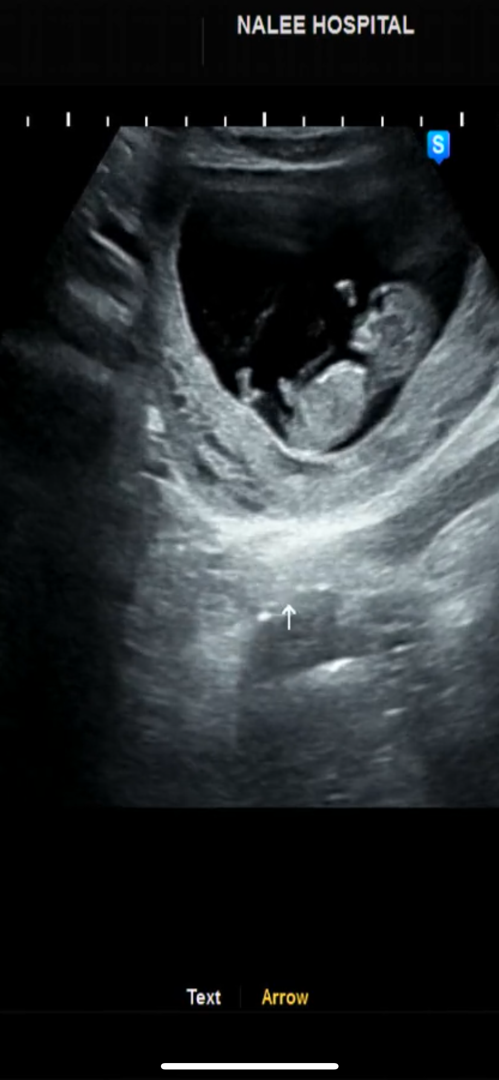

11주로 성별 알수있나요?

11주 진료보고 13주에 가는데 궁금해서 올려봅니다!